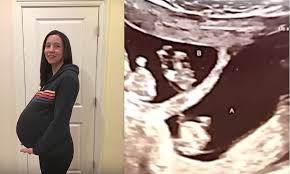

Gravid Etter 45: Nå, ganske nøyaktig tre år senere, venter de sitt første barn sammen.